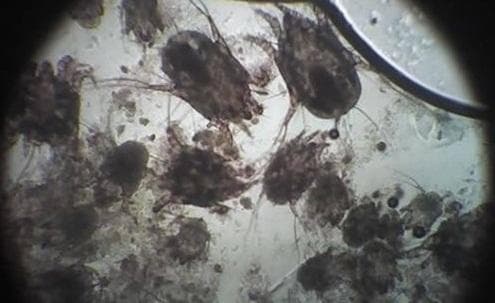

Главный признак отодектоза – сильный зуд в области ушной раковины. Если заглянуть в ухо собаки с отодектозом, то мы увидим темно-коричневый, почти черный налет. Иногда его так много, что он в буквальном смысле «отваливается кусками», образуя корки. Для диагностики отодектоза достаточно исследования мазка из наружного слухового прохода под микроскопом. Клещи, размер которых достигает 0,5 мм, обычно хорошо видны даже при небольшом увеличении. Также может проводиться так называемый “тест на черной бумаге” - клещи имеют белесую окраску и движение мелких светлых точек может быть замечено даже без микроскопа.